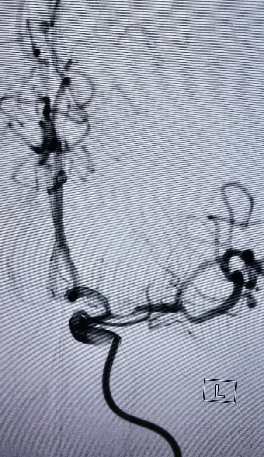

导丝怎么扩【载药时代 球扩天下】NOVA DES®颅内药物洗脱支架在大脑中动脉重度狭窄中的应用两例!_https://www.jmylbn.com_新闻资讯_第14张

导丝怎么扩【载药时代 球扩天下】NOVA DES®颅内药物洗脱支架在大脑中动脉重度狭窄中的应用两例!_https://www.jmylbn.com_新闻资讯_第15张

重要影像结论左侧基底节区、放射冠、左侧颞枕、顶、额多发脑梗塞,左侧大脑中动脉M1段狭窄。